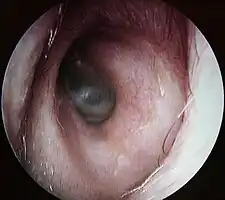

Conduit auditif externe gauche, au fond le tympan